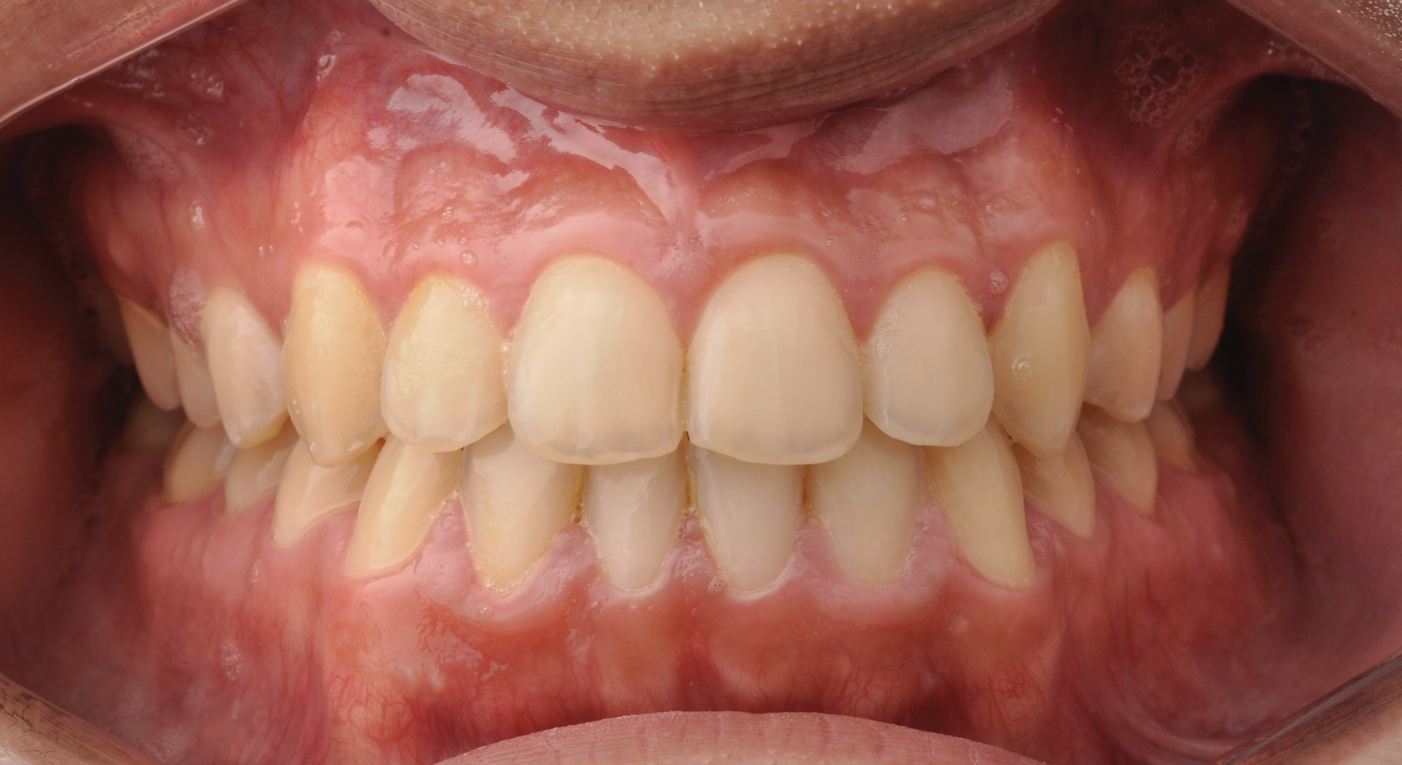

Fig 10. Postsurgical orthodontics for bite settling after the surgical procedure. Surgery for this patient consisted of maxillary surgical advancement, mandibular surgical asymmetric setback, and genioplasty (chin correction). Note the anterior and posterior crossbite was corrected and a class I occlusion was obtained.

Figure 10